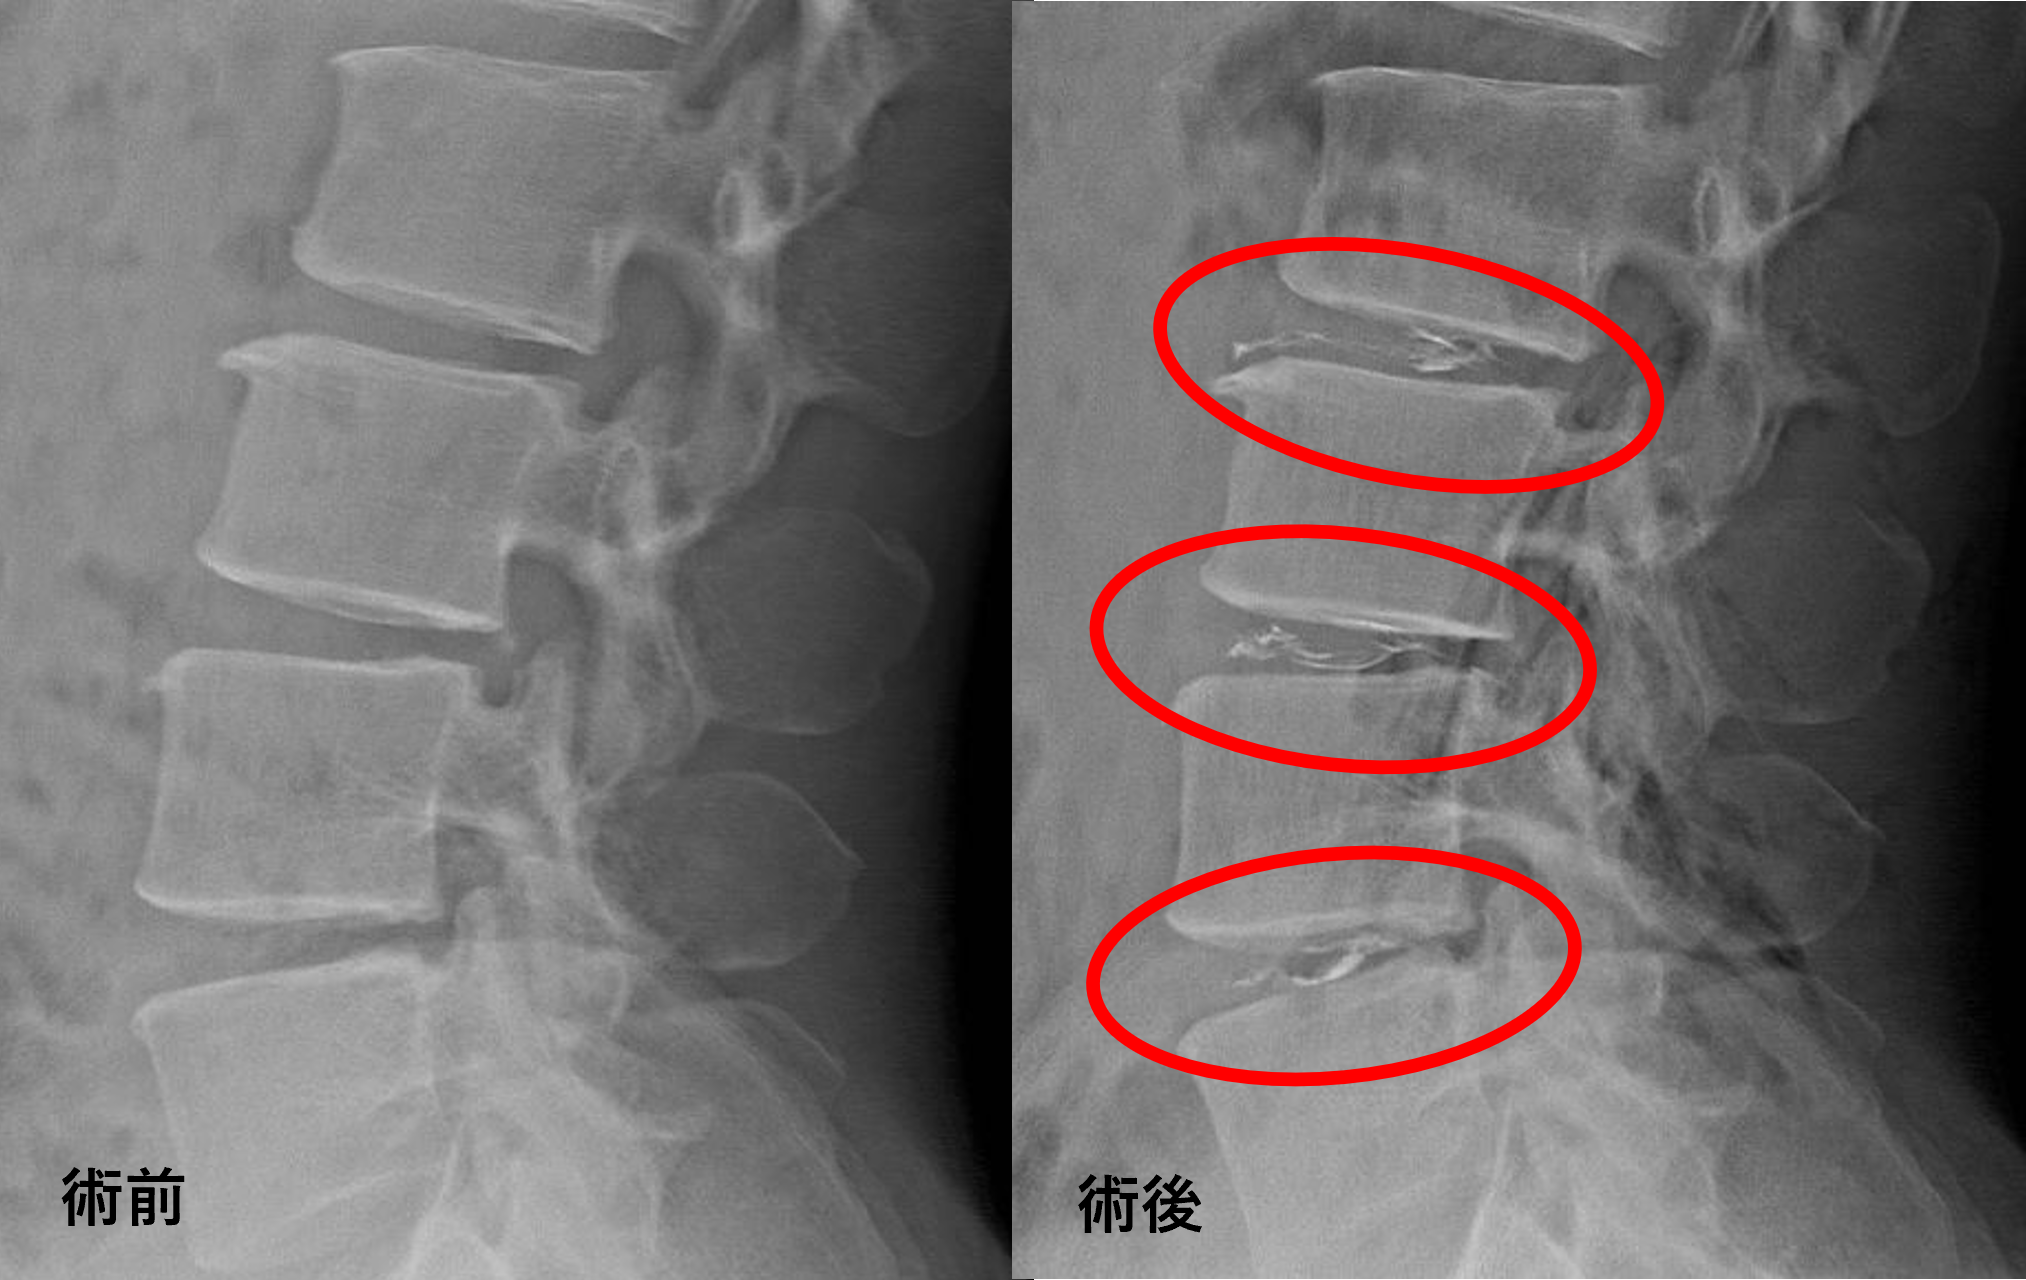

画像及び所見について

- L2/3、3/4、4/5 – 椎間板変性、膨隆

以上のことが画像上認められました。

L2/3、3/4、4/5の椎間板所見による脊柱管の圧排が、症状の原因の可能性が高い。

患者様と相談の元、L2/3、3/4、4/5にセルゲル法を施行